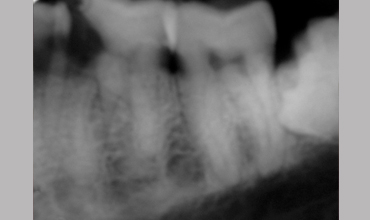

Management Of Radix Entomolaris In Mandibular First Molar